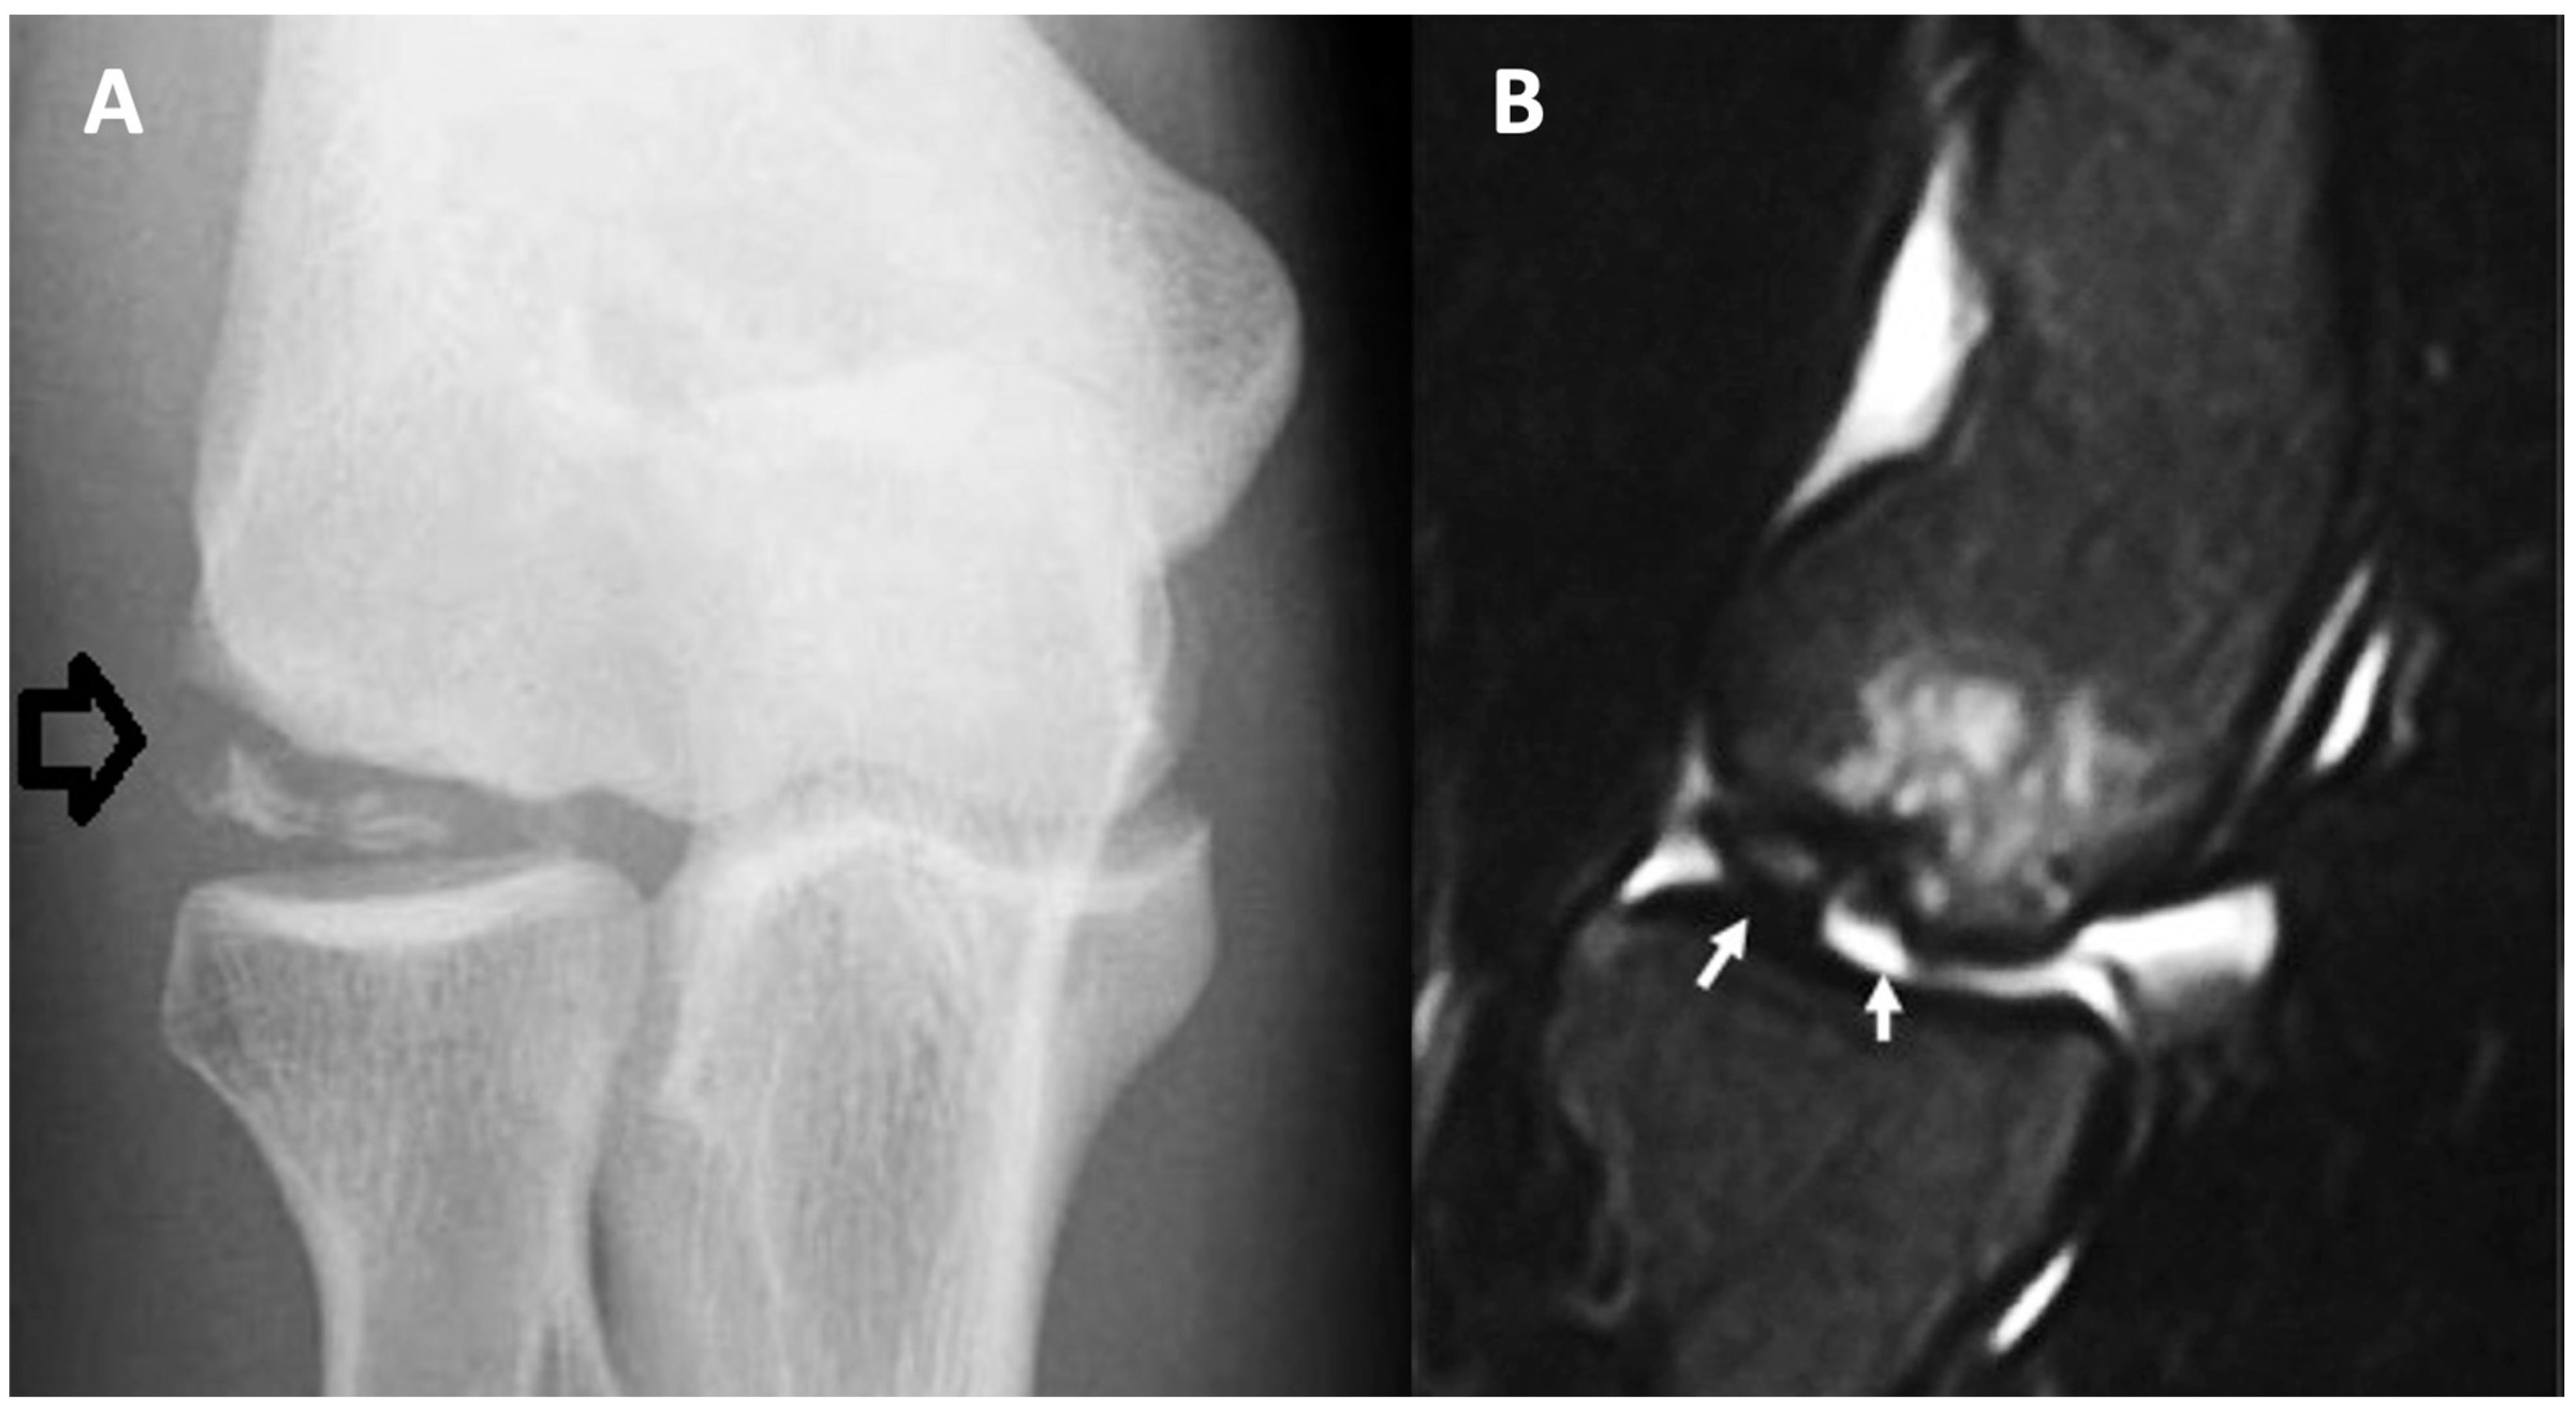

Radiography is the primary method for diagnosing and tracking the progress of OCD treatment. It is also advisable to conduct bilateral and standing alignment radiographs since bilateral OCD of the knee may occurs in 14–30% cases [17,38,39]. Early stages of OCD may show changes in the contour and radiolucency near the joint surface on radiographs (Figure 1A). More progressed stages often reveal a distinct, sometimes ossified fragment (referred to as the progeny), separated from the main bone (the parent) by a crescent-shaped radiolucent line, which might ossify as the healing progresses [17].

Figure 1.

Radiographic (A) and computed tomography (B) pictures of humeral OCD. Arrows indicate OCD in the humeral head.